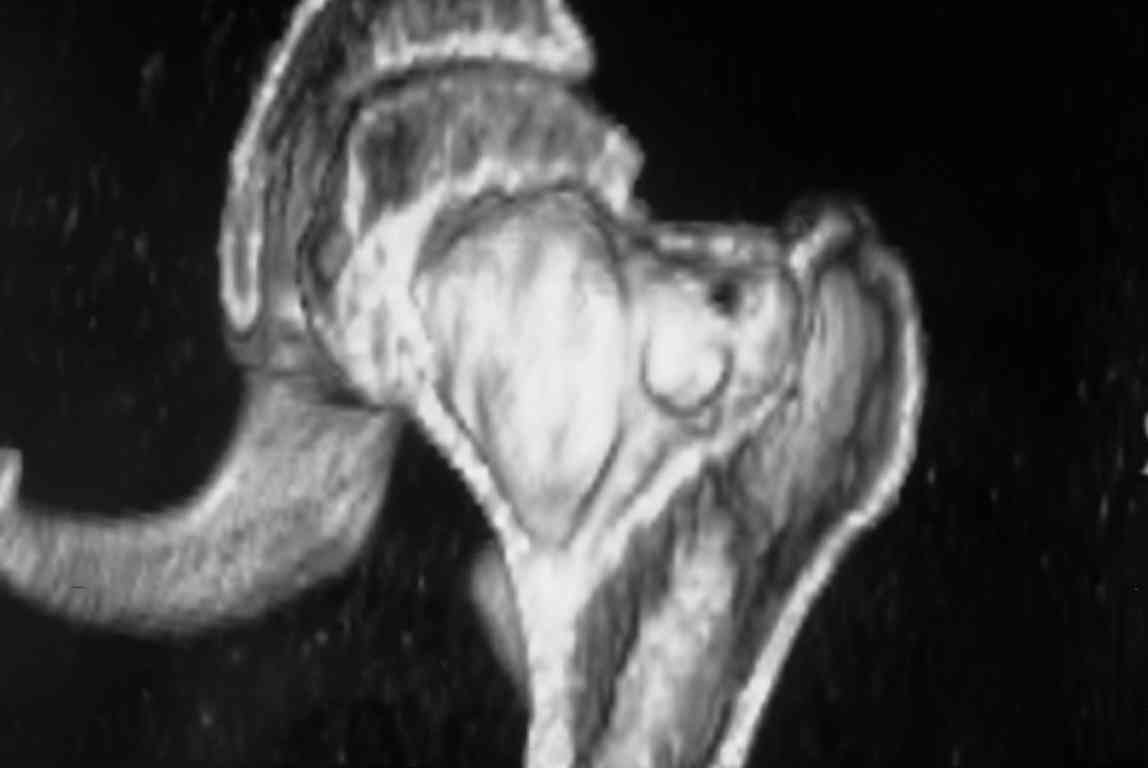

Больная Л.,   23 года.

Из анамнеза:со слов больной в 2006 г. появились боли правой н/конечности, обратилась поместу жительства к хирургу, было выполнена МРТ поясничного отдела позвоночника,назначено физиолечение. Через 2 месяца боли прекратились, через 4 месяца рецидивболевого синдрома. С 2006 – 2010 проводилось консервативное лечение по поводуостеохондроза поясничного отдела позвоночника. В октябре 2010 г. боли усилились.Выполнены Ro и КТправого тазобедренного сустава, выявлен очаг патологической перестройки. Быланаправлена на консультацию в УНИИТО.

В УНИИТО виюне 2011 г. поставлен дифференциальный диагноз между фибромой, солитарной костнойкистой и гигантоклеточной опухолью.

Наши предложение по выборулечения:

1)     эндопротезирование тазобедренного сустава;

2)      при выявлении ОБК – заполнение полости костным цементом;

3)     в случае фибромы – заполнение полости аллокостью.

Вариант пластикиаутокостью не подходит, т.к пациентка субтильного телосложения.